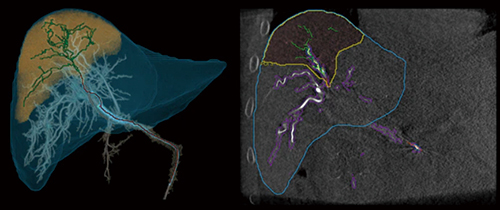

■AFDのさらなる進化:“Liver ASSIST Virtual Parenchyma”の登場

そして,2020年の北米放射線学会(RSNA)にて,再び肝臓領域の新たなアプリケーションとして紹介させていただいたのが,“Liver ASSIST Virtual Parenchyma”(以下,LAVP)である(図5)。弊社が得意とするディープラーニングを用いたビッグデータ解析技術により開発されている。

LAVPでは,特定の栄養血管上にカーソルを置くことで,その枝から塞栓されるであろう肝臓の区域を画像表示できる機能が新たに加わった。Liver ASSIST V.I.の結果とともに,カーソル位置に応じたVirtual Injection,ならびに塞栓予測範囲とその境界線を表示可能である(図6)。

図5 Liver ASSIST Virtual Parenchyma

図6 ターゲットに連続性のない栄養血管の場合のLAVP結果